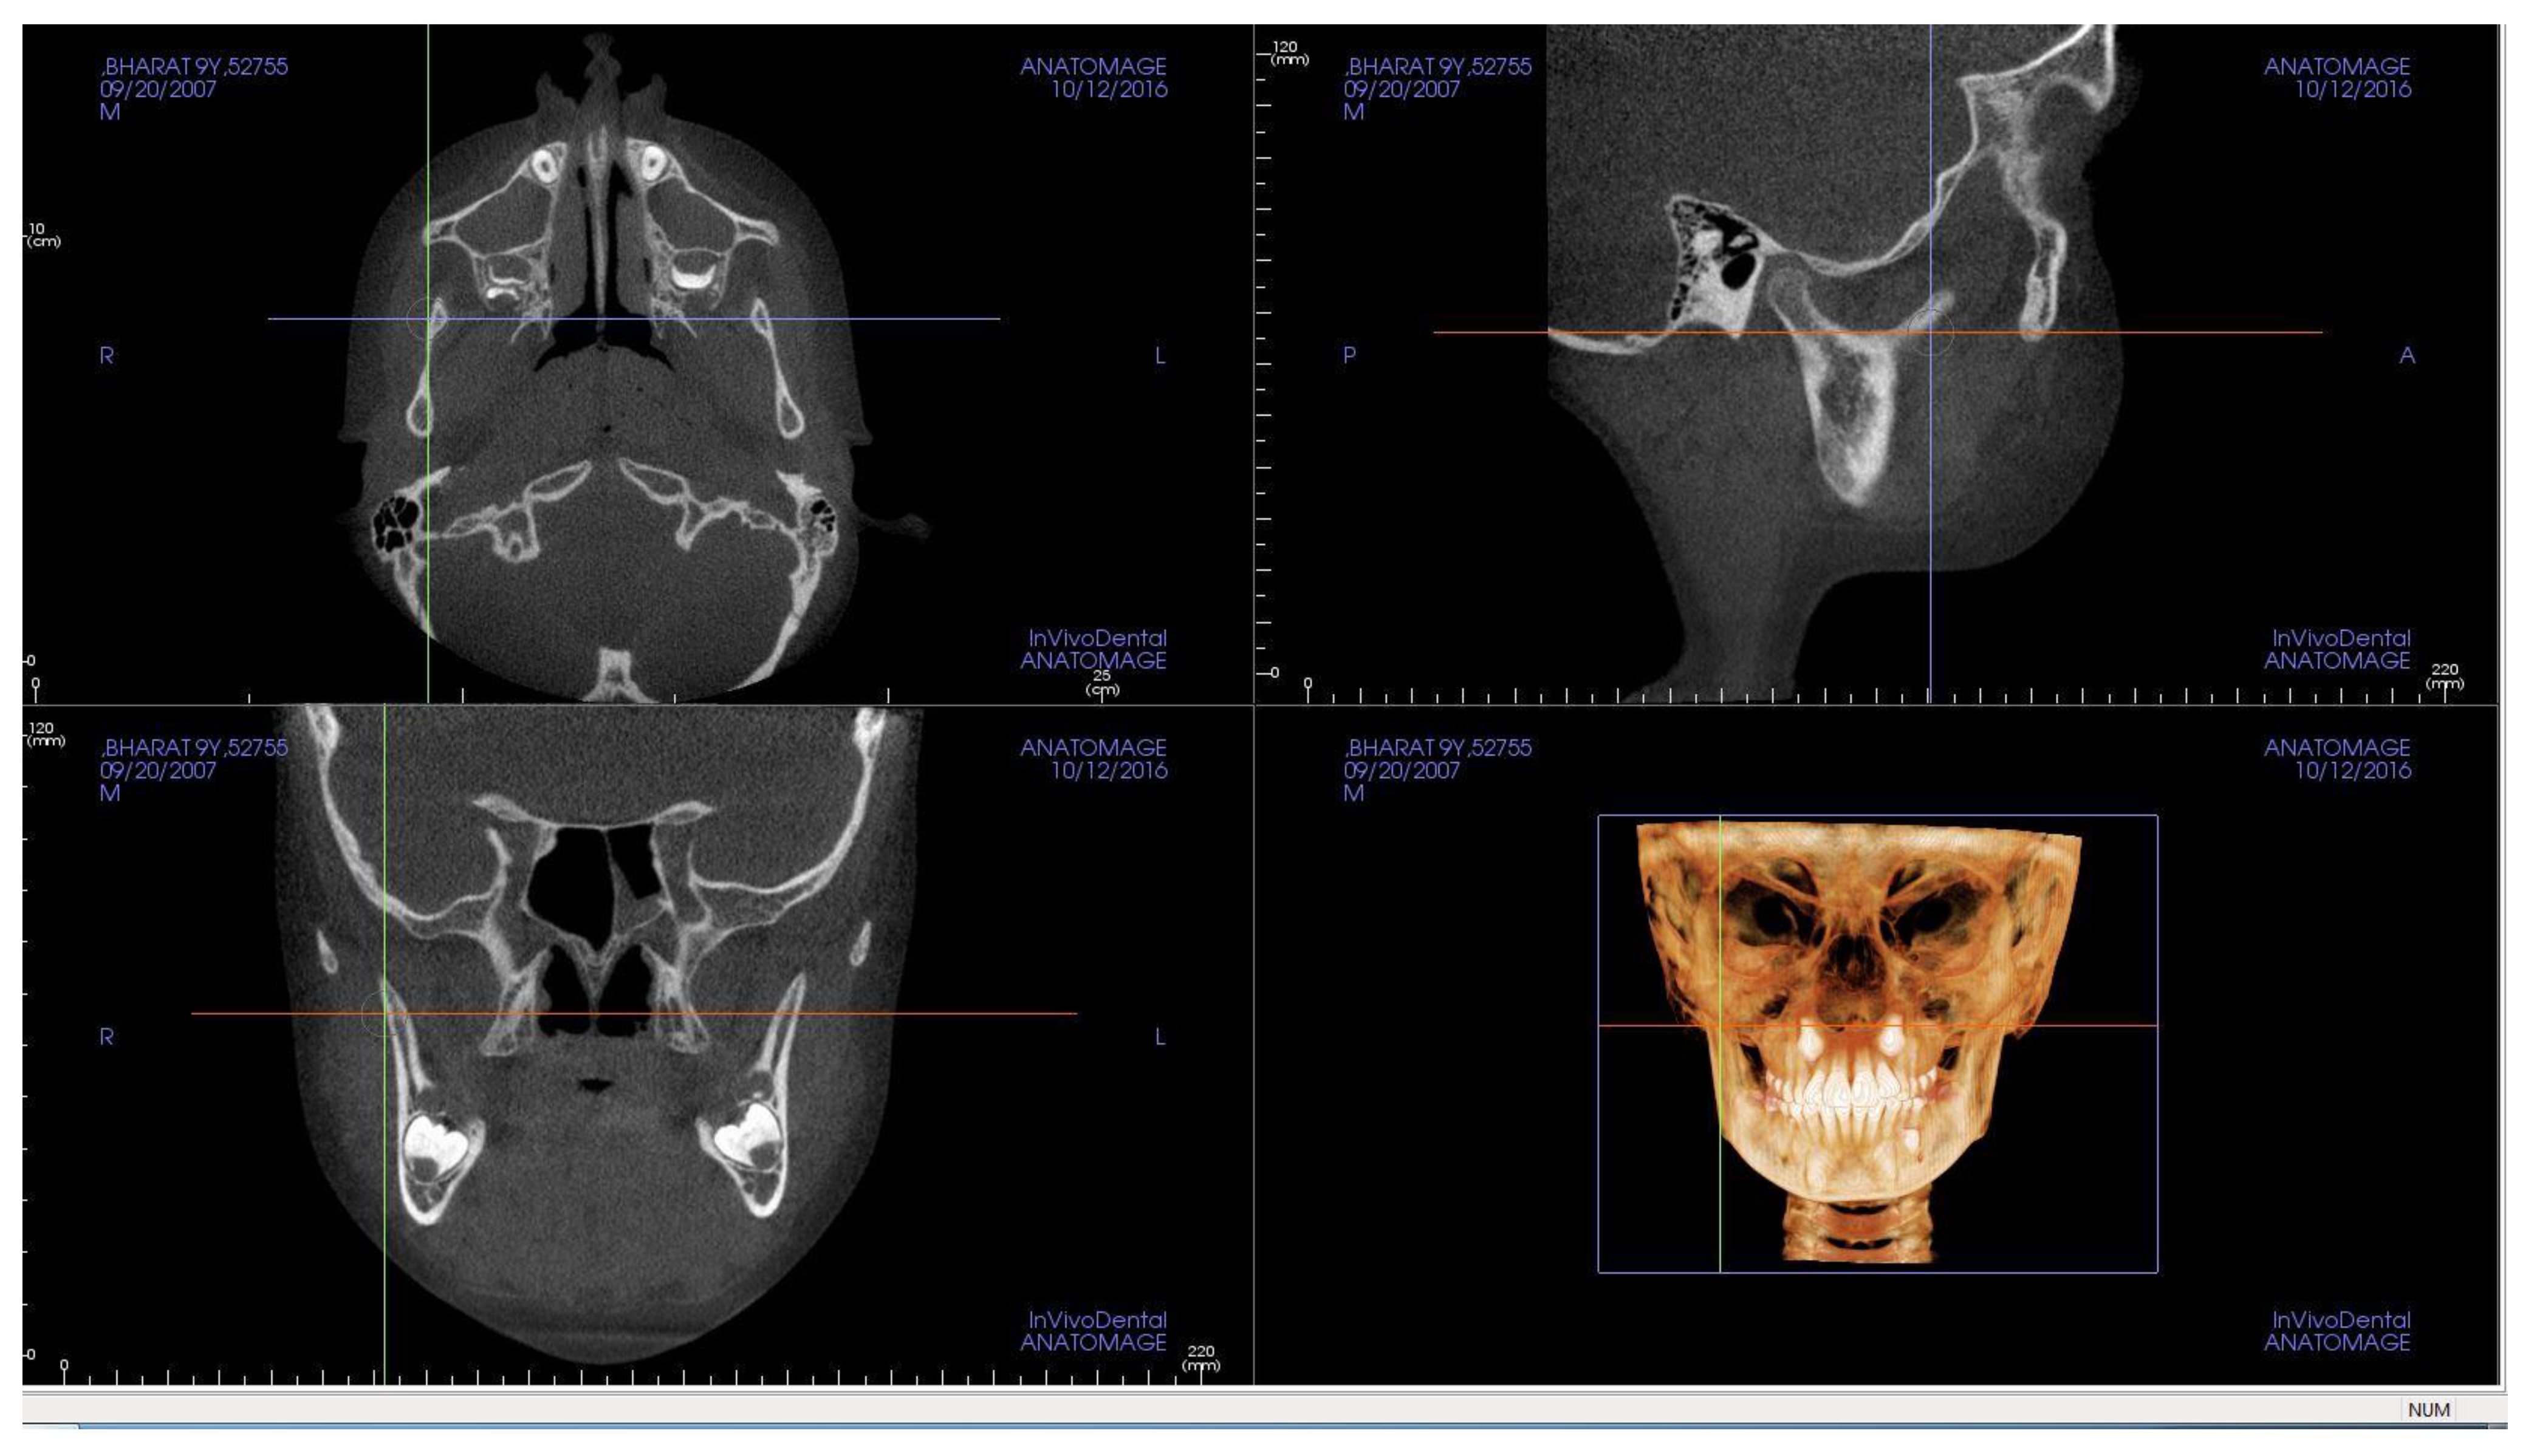

2. Materials and Methods